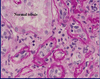

Acute Tubular Necrosis (main photo); normal photo in bottom Right corner; ATN most commonly affects the Prox. CT and can be caused by ischemia or toxins

Ischemic ATN; caused by shock, hypovolemia, and hypoxemia; usually milder than toxic ATN, the tubular epi. cells fall off individually.

ATN urine sediment; contains epithelial cells and necrotic debris

Tubular necrosis; necrotic cells slough off into the tubular lumen; seen in Acute TID

Edema; seen in interstitium as foamy/vacuoles between tubules. Characteristic of Acute TID